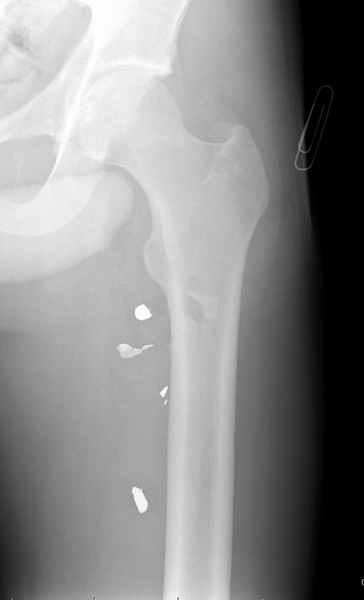

Больной с огнестрельным переломом бедра с вовлечением около 15% медиального кортекса, входное отверстие около 1 см в диаметре; стабильный, без сосудистых и неврологических признаков.

Что делать: гипс, костыли, операция?